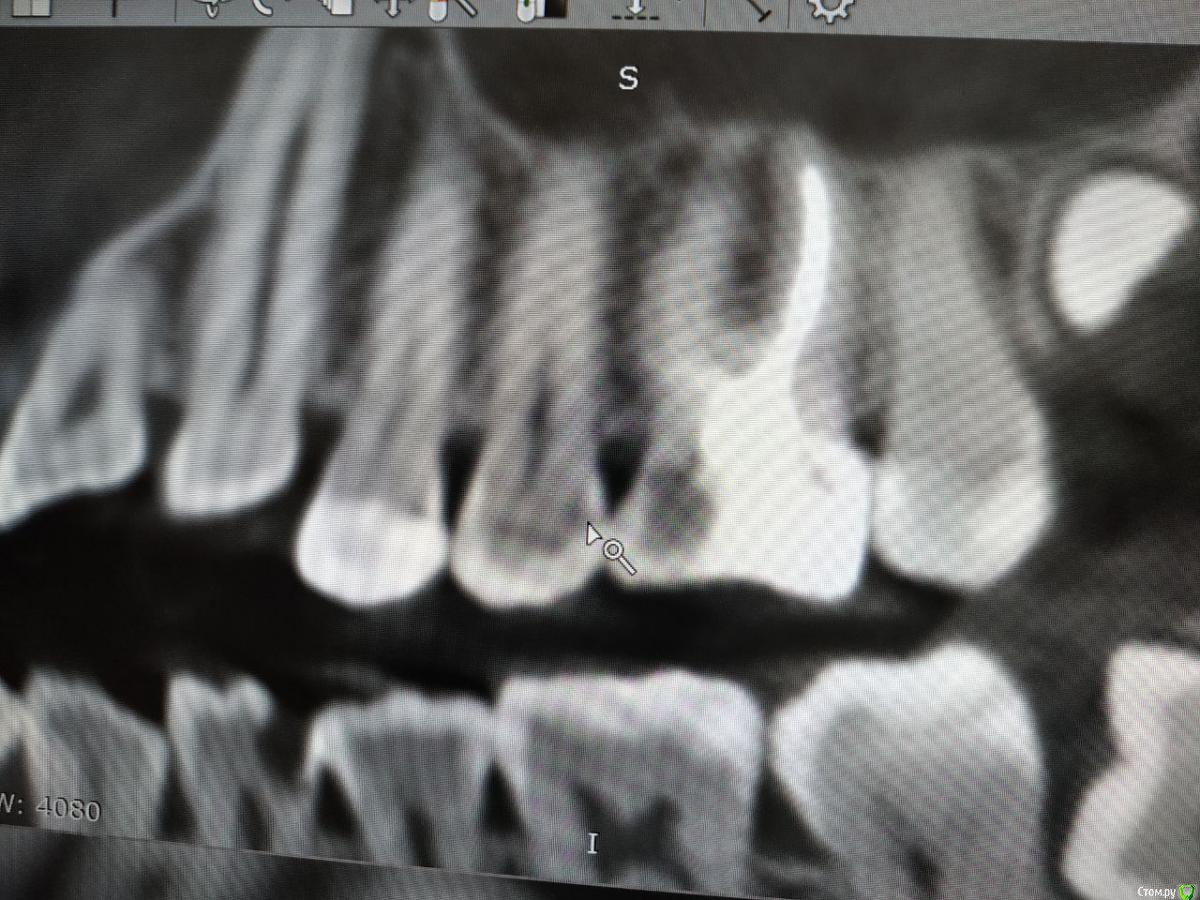

red_butler Опубликовано 4 февраля, 2020 Поделиться Опубликовано 4 февраля, 2020 Покажите ещё срезы Кт Ссылка на комментарий

Liza544 Опубликовано 4 февраля, 2020 Автор Поделиться Опубликовано 4 февраля, 2020 Вот еще пару снимков которые у меня есть. ПРошу заметить, что последние 4 снимка (файлы 7-10), которые я тут прикрепила - до пломбы на 25-м зубе и до залеченного 4-го канала в 26-м зубе. Подскажите пожалуйста, может ли быть зуб недостаточно залечен, хотя на КТ ничего подозрительного не видно? Ссылка на комментарий

ЛанаМ Опубликовано 4 февраля, 2020 Поделиться Опубликовано 4 февраля, 2020 Воспаление десны может давать постоянные ноющие боли и боль при накусывании. От чистки сразу не пройдет, нужно дней 5-7 противоспалительного лечения и отсутствие травмирования (постараться ниткой не чистить). Также нужно убедиться, что нет хронического воспаления в гайморовой пазухе. Побольше срезов кт, желательно уже после пломбирования четвертого канала. Да, бывают проблемы в зубе и при идеальной картинке рентгеновского снимка. На нем видны только крупные каналы, а там еще целая сеть мелких. Ссылка на комментарий